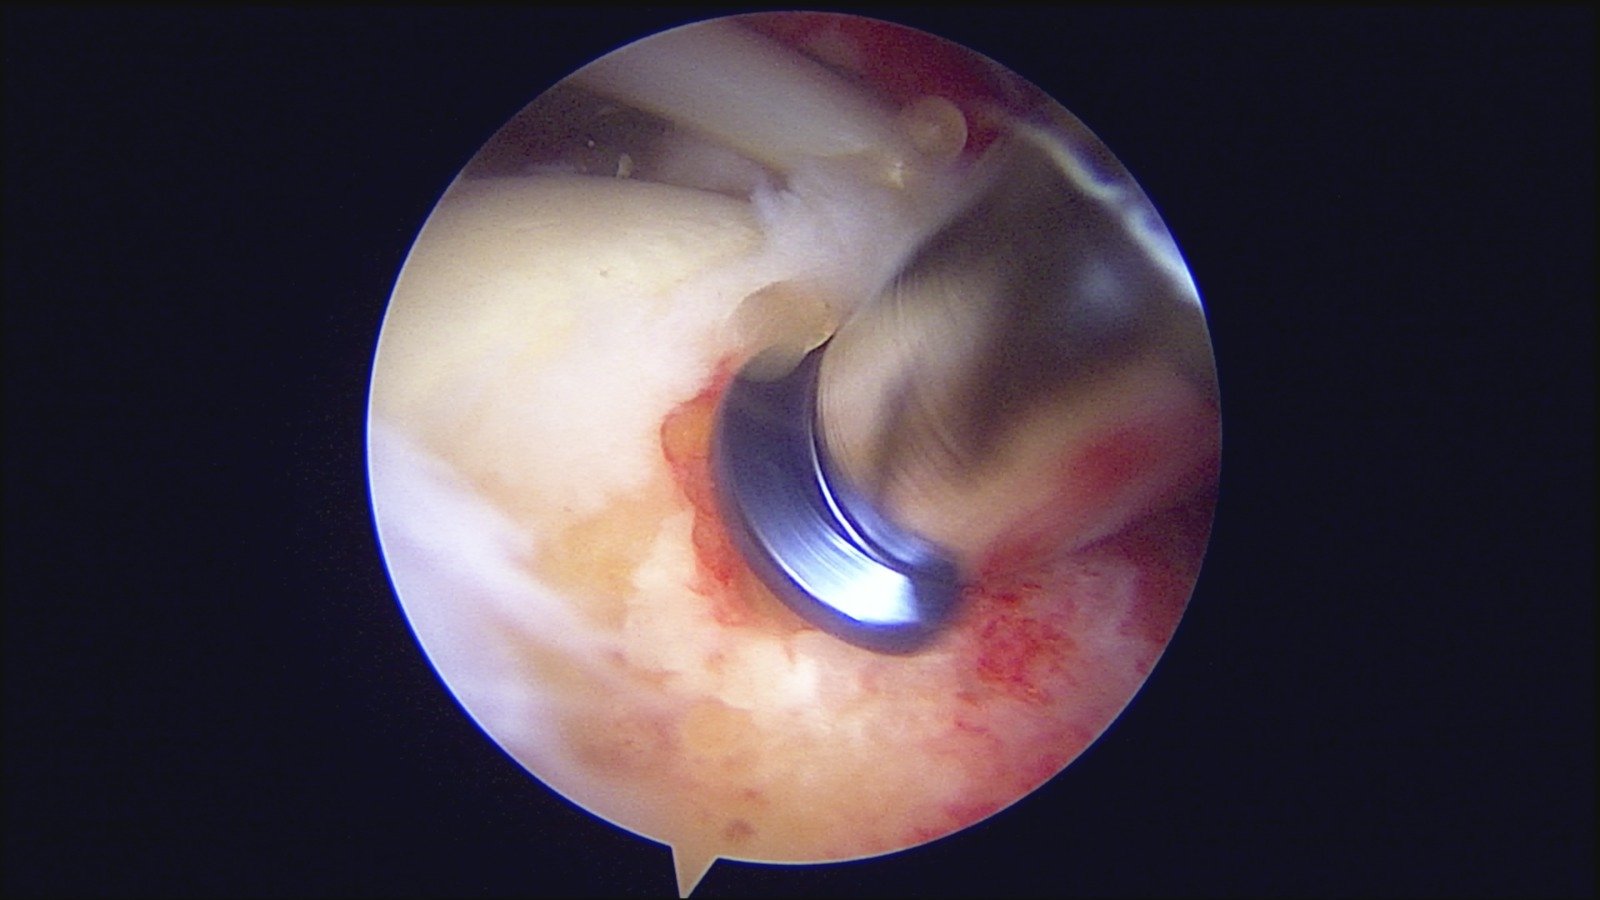

GalleryShoulder rotator cuff repair Meniscus root repair Meniscus repair Bankart repair for recurrent shoulder dislocation ACL reconstruction Machines Instruments